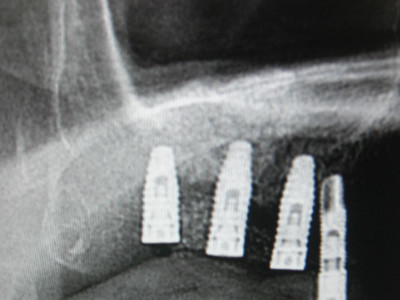

最後の2枚は定期チェックにいらっしゃった患者様の画像です、ご了解の上でアップさせて頂きました、サイナス後、9年ほど経過しておりますがしっかり噛み込めており問題なしです。